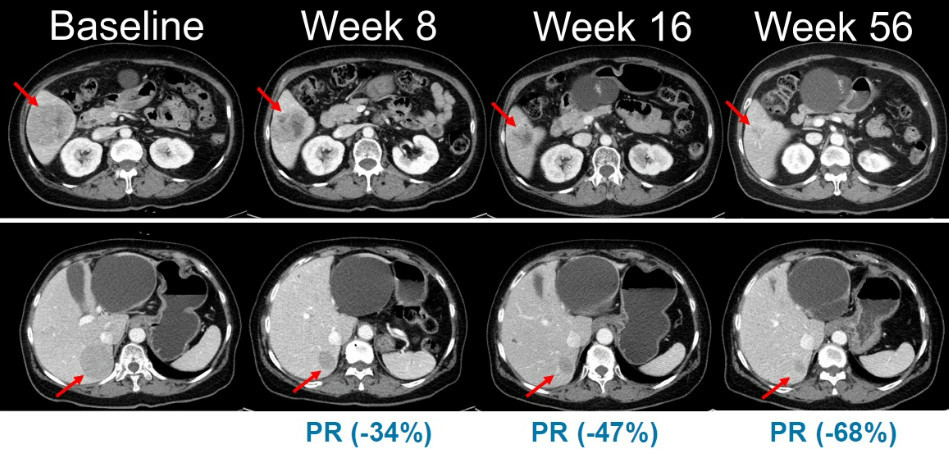

한미사이언스 핵심 사업회사 한미약품은 지난 12일 국내 대학병원에서 NRAS 돌연변이를 보유한 국소 진행성 또는 전이성 흑색종 환자를 대상으로 벨바라페닙(Belvarafenib)을 평가하는 2상 임상시험에 참여하는 첫 번째 환자를 등록하고 첫 투약을 완료했다. 지난 1월 식품의약품안전처로부터 임상 2상 시험계획서(IND)를 승인받은 이후 실제 환자 투약까지 불과 한 달여 만에 신속하게 이뤄진 성과다. 이번 임상은 총 45명의 환자를 대상으로 벨바라페닙과 MEK 억제제인 코비메티닙(Cobimetinib) 병용요법의 유효성과 안전성을 평가하는 다기관, 단일군 시험으로 전개된다.

벨바라페닙과 코비메티닙의 병용요법은 기존 BRAF 단일체 및 MEK 억제제 조합이 가진 기전적 결함을 보완하는 전략으로 평가받는다. 보다 폭넓은 유전자 변이 환자군에게 임상적 이점을 제공할 수 있는 가능성을 열어둔 셈이다. 한미약품 ONCO임상팀 노영수 이사는 이번 임상 2상을 통해 NRAS 변이 흑색종 환자군에서 치료 효력을 면밀히 확인하고 임상 개발을 체계적이고 속도감 있게 수행해 유의미한 결과물을 도출하겠다는 의지를 보였다.